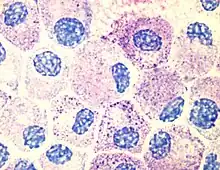

Mast cells.

Most histamine in the body is generated in granules in mast cells and in white blood cells (leukocytes) called basophils. Mast cells are especially numerous at sites of potential injury – the nose, mouth, and feet, internal body surfaces, and blood vessels. Non-mast cell histamine is found in several tissues, including the hypothalamus region of the brain, where it functions as a neurotransmitter. Another important site of histamine storage and release is the enterochromaffin-like (ECL) cell of the stomach.